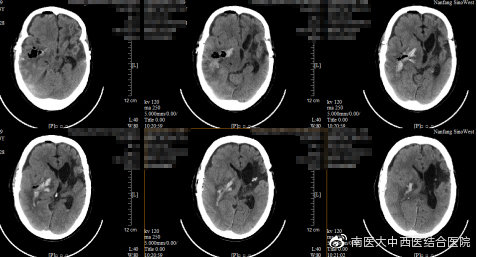

血肿清除术后CT